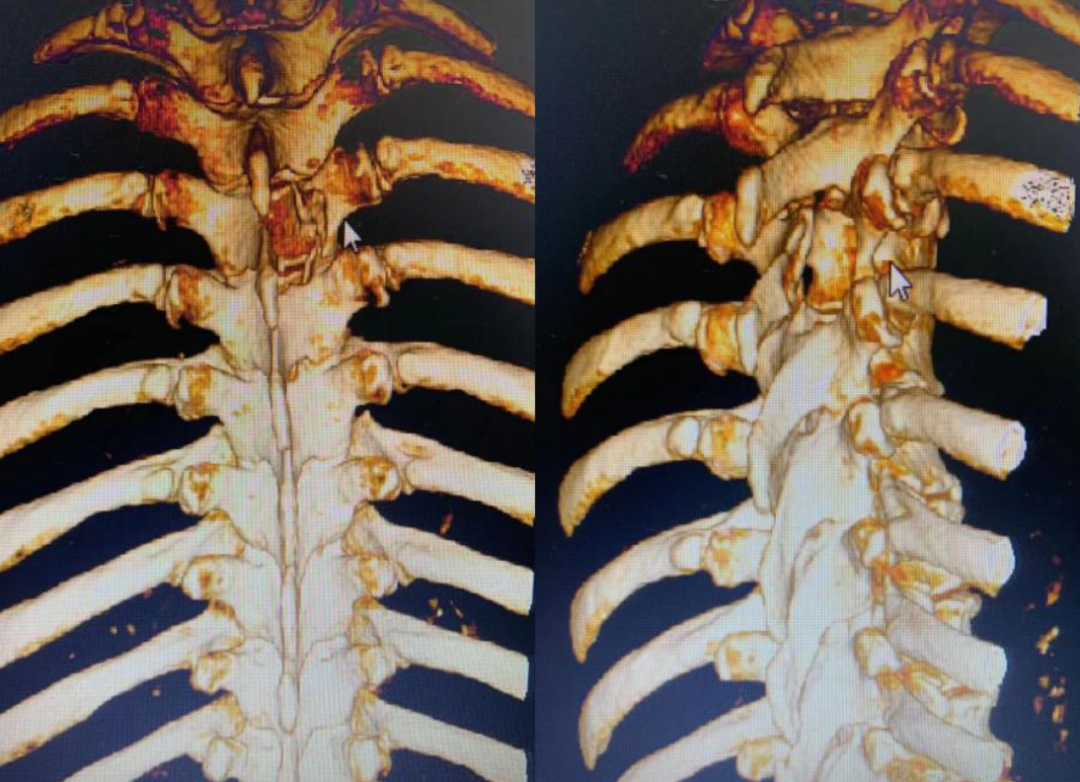

敲定了手术方式,手术如期进行。在徐杰的引导下,“天玑”灵活地挥动着机械臂,紧贴肿瘤边缘,磨出一个近似长方体的区域,很快就将肿瘤位置锁定。随后,徐杰娴熟地运用他自创的手术方式切除了整个肿瘤,术后影像显示肿瘤切除范围与术前规划几乎完全一致。

手术时,医生将病人的三维CT图像导入机器人图像系统,主刀医生在机器人系统的计算机上,用鼠标规划好在脊椎椎板上开窗的最小边界和最佳斜率方向,路径边界避开了重要的结构并保留脊柱关节突;随后,启动机器人的机械臂,自动精确走位到该边界,利用携带的磨钻直接在脊椎上开一小窗。然后,医生在显微镜下用显微外科技术打开脊髓神经的硬膜,完整切除肿瘤,该肿瘤为钙化性脊膜瘤。

该手术方法的意义是,医生创新设计了一种从“定点到定点连续移动”的机械臂指令,实现用最小的椎板开窗,保留关节突等重要结构,避免了使用内固定。且术中无需放置引流管,让皮肤手术切口缩小到2.5厘米,病人康复时间加快。